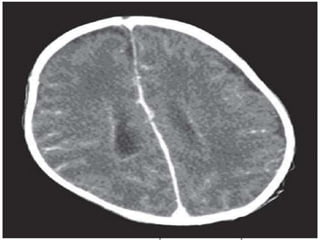

• subfalcine herniation

Subfalcine herniation

Midline shift